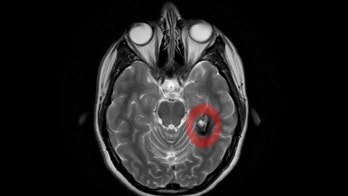

Head Injury February 16, 2017 Brain tumor triggers woman's sudden 'hyper-religious' behavior A woman in Spain who suddenly became very religious and believed she was speaking with the Virgin Mary turned out to have a brain tumor that appears to have caused her symptoms, according to a new report of the case.